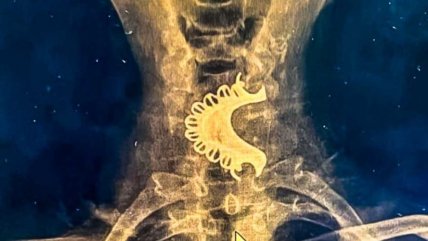

Adulto mayor se tragó su dentadura postiza y pasó cuatro días con ella en la garganta